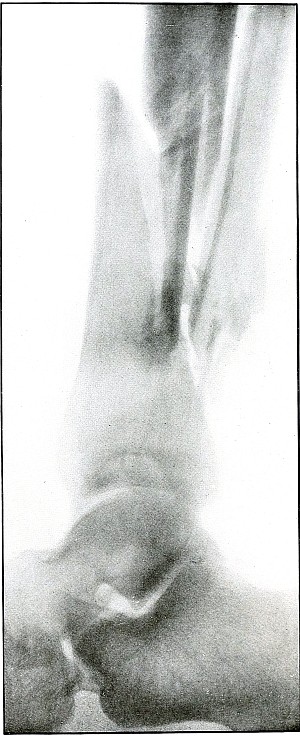

Plate 59.

_

[Pg 129]

Rifle—Plate 59.

LOWER EXTREMITY.

Gunshot Wound of the Left Knee-Joint,

with Lodgment of the Missile in the Joint.

The course of the bullet was transverse, entering the capsule posterior to the patella without injury to the bone.

As its shadow projection is almost circular, the bullet must be standing almost on its end pointing toward the plate with its long axis almost parallel to the line of projection.

As the fibular side of the leg lay next to the plate and as the only slightly enlarged shadow of the bullet indicates it to be near the plate, its position is in the joint near the fibular side.

As the bullet is undeformed and its penetrating power very slight, its velocity was that of extreme range.

The emergency treatment, is, of course, a simple antiseptic dressing with the leg held in the most comfortable position by muscular action.

The subsequent treatment is removal of the bullet when proper surgical conditions obtain. [Pg 130]